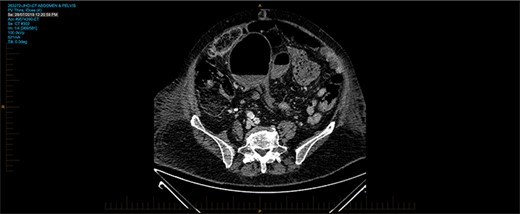

A 93-year-old patient who has history of recurrent sigmoid volvulus presented with a week of abdominal distension and bowels not working. Initial blood test revealed that she has white cell count 11.3 × 109/L, CRP 12 and lactate of 1.9. CT abdomen was performed on admission showed features of sigmoid volvulus. Patient was booked for flexible sigmoidoscopy to decompress the sigmoid volvulus. Flexible sigmoidoscopy revealed that there was significant mucosal necrosis of the sigmoid colon. A diagnostic laparoscopy was performed to determine the severity of necrosis. Laparoscopy reported that the sigmoid colon was oedematous but no signs of transmural necrosis. Patient was kept in the hospital for observation but there were no signs of improvement. Day 4 of the admission, patient continues to deteriorate clinically and had a medical emergency team response call for worsening pain and hypotension, and a repeat CT abdomen was performed. The images were consistent with sigmoid volvulus through transmesocolon defect resulting an internal hernia (Figure 5–7). The patient had emergency laparotomy. The sigmoid colon was found to be in the supracolic compartment and required decompression prior to reduction (Figure 1–4). There was transmural necrosis close to the rectosigmoid junction. Patient underwent Hartmann procedure. Patient recovered well postoperatively and discharged to home.

CT on axial view showing twisting of sigmoid colon resulting in volvulus.